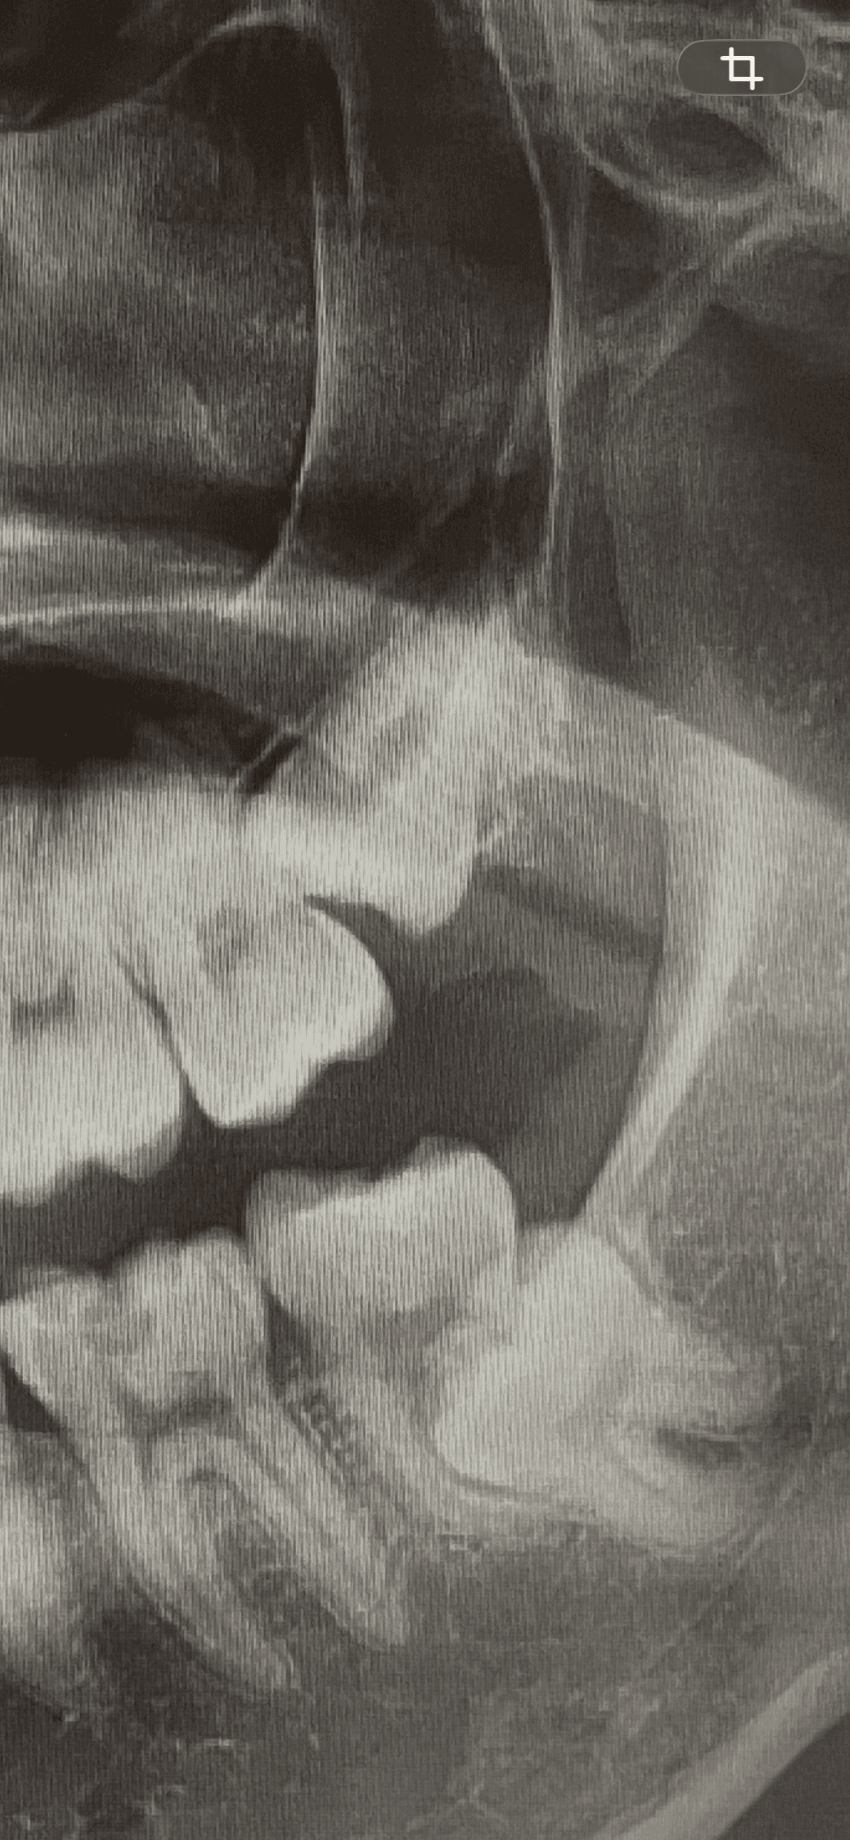

2.

LvMVjl

elWeRe